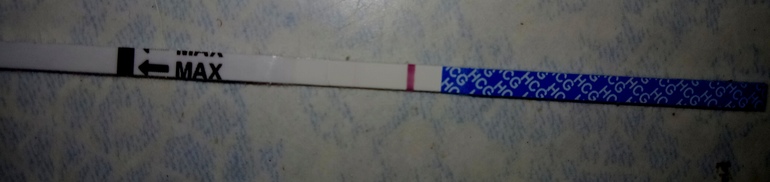

8 ДПО

Девочки, что скажите.? Вроде рано ещё, ну я её вижу.

Есть, конечно же

Ярчайте, будьте здоровы

Эти тесты мне не врали.